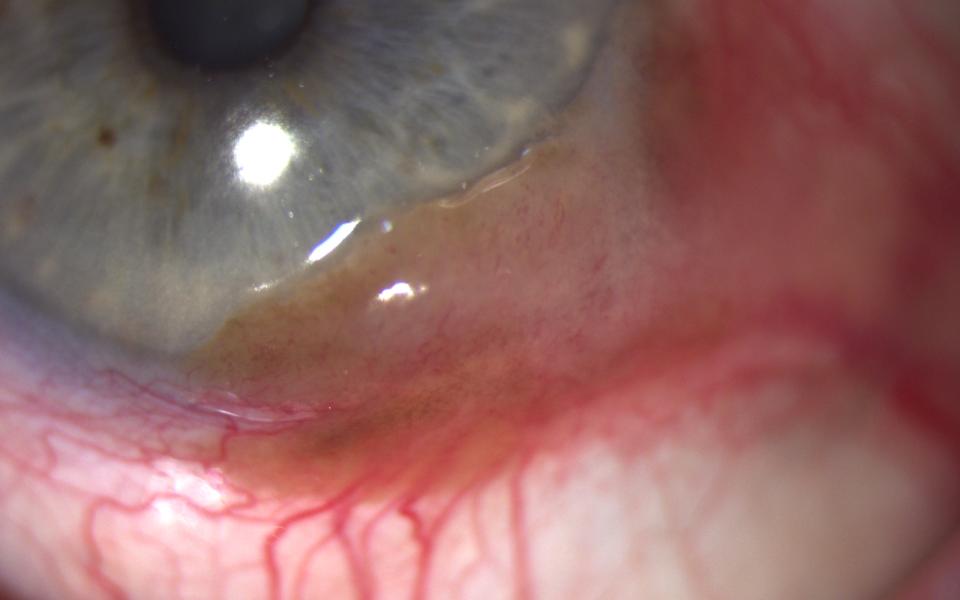

78 Male presenting with blurring of vision for 4 months. Slit lamp examination demonstrated corneal OSSN, with characteristic fimbriated margin. He was commenced on topical interferon alpha-2b 1